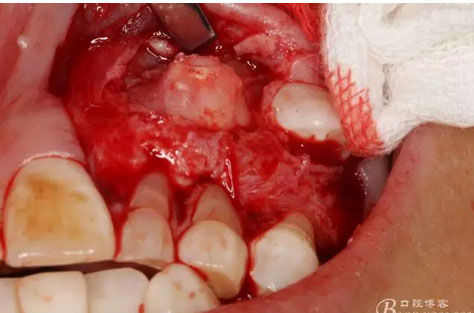

圖18.摘除囊腫后遺留的巨大骨腔

圖24.摘除的牙瘤組織及拔除的23牙齒。